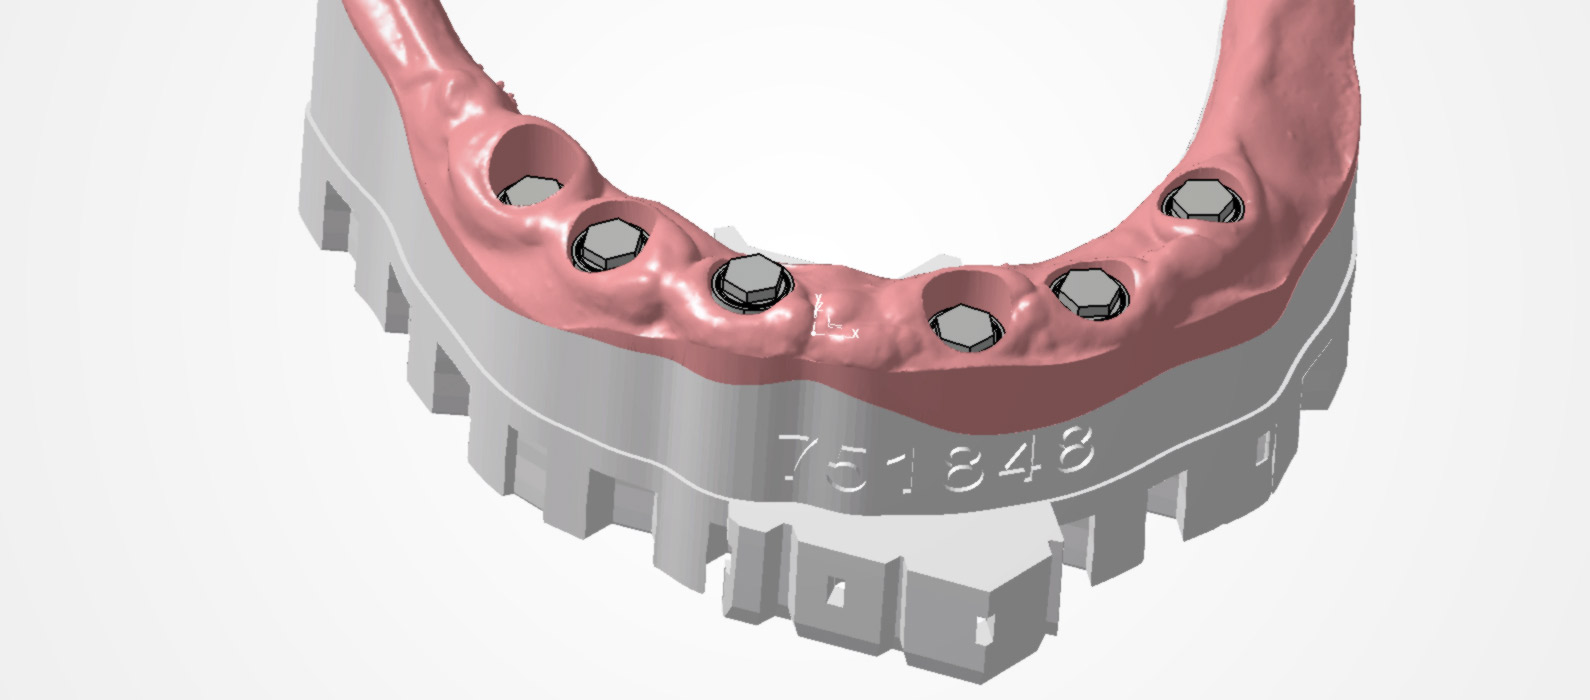

Road to smile

RoadToSmile è un progetto che ha l'obiettivo di ricercare e sviluppare nuovi processi di pianificazione per trattamenti protesici chirurgici e dentali utilizzando le ultime tecnologie. Il progetto è finanziato dal Programma Hazitek del Governo Basco.

Progetto IOPREC

L'obiettivo del progetto IOPREC è quello di sviluppare un sistema di correzione fisico-digitale per scansioni intraorali di precisione, al fine di ottenere protesi dentali supportate da impianti per pazienti edentuli.